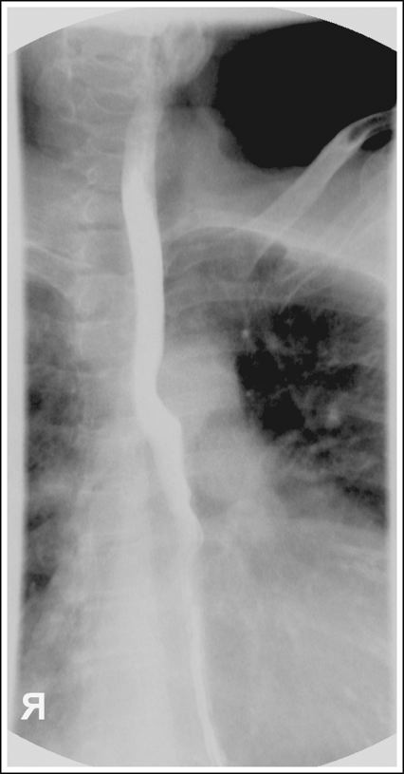

Lateral Esophagus (Right or Left (CR and Positioning)

Recumbent lateral position - preferably right lateral and facing radiographer

Arms forward

MCP centered

Shield patient

Place IR at the top of the mouth

CR at the level of T5-T6

Instruct patient to take big swallows and expose while esophagus is full of barium

Lateral Esophagram Eval Criteria

Arm not interfering with esophagus

Ribs posterior to the vertebrae superimposed with no rotation

Lateral esophagus with proper positioning

Lateral esophagus with superior and middle no barium